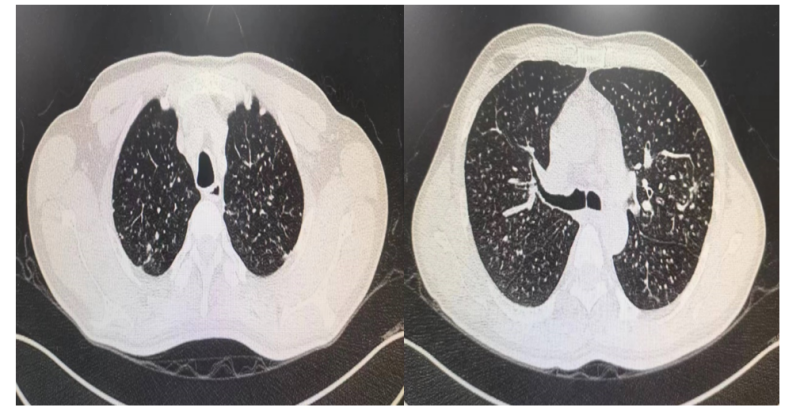

患者吴某,男性,45岁,因"反复咳嗽1年多,伴气喘3月余"于5月21日就诊南溪山医院呼吸与危重症医学科一区,入院查肺部 CT显示两肺多发异常密度影,考虑职业相关性肺疾病,经追问病史,得知患者从事石头打磨工作多年,结合病史考虑患者肺部病变为尘肺可能性大。经呼吸一区佘巍巍博士团队分析患者病情后,发现患者肺部病变明显,有大容量肺泡灌洗术指征,经与患者详细沟通病情后,患者及家属积极同意配合治疗。

图一 肺部CT